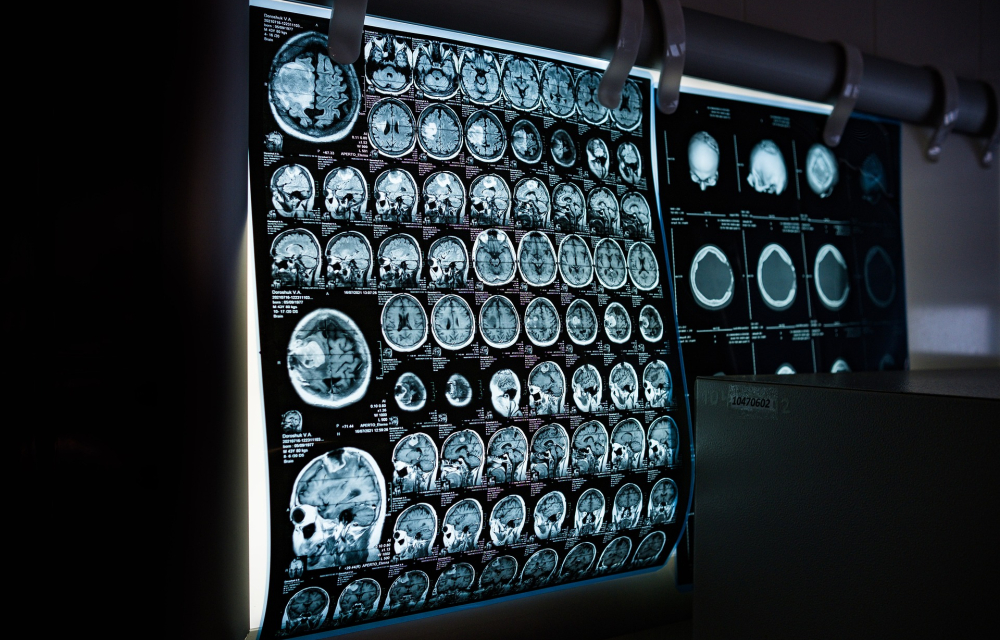

MRI

Ny upptäckten av hjärnforskare vid Uppsala universitet.

Foto: Pixabay